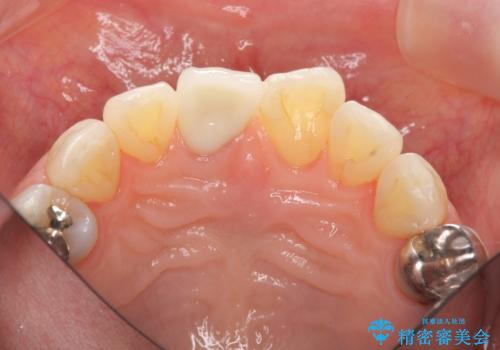

前歯の変色 セラミック審美補綴

- 前歯の変色の改善を希望され来院されました.

以前に神経が死に、根管治療を行った歯の変色が認められたためセラミックによる審美補綴治療を計画します。

- 16万円(仮歯・ファイバーコア・ジルコニアクラウンスペシャル)費用は治療当時の料金となります

神経の死んでいる歯について

神経治療を行い補綴(かぶせもの)治療を行わないと、変色が目立ち審美障害を起こすことがあります。

このような場合、セラミックによる審美改善が治療の一案として提案されます。